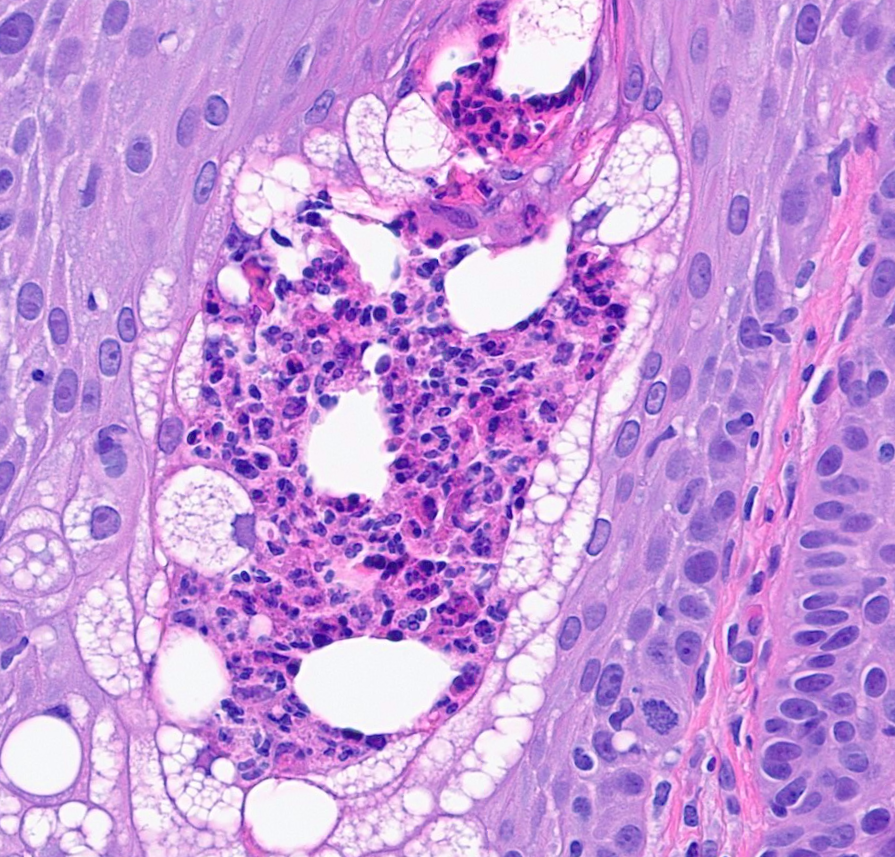

I'm so honored to receive the Dermatopathology Trainee World Cup 1st place for my presentation on cysts mimicking malignancies with Drs. Foulis and Gibbs! Had a great time, learned a lot, and met many amazing people @IntSocDermpath #ISDP2023 #PathTwitter #dermpath #dermtwitter